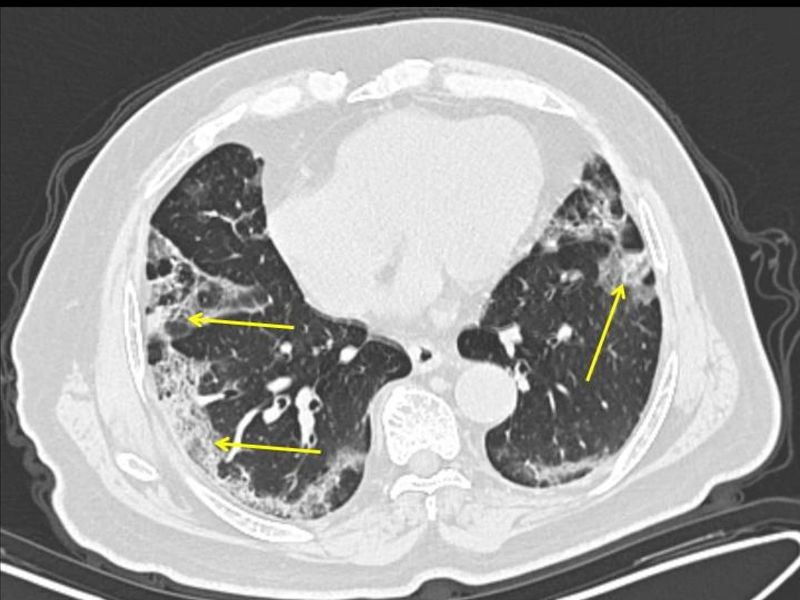

Hình ảnh chụp CT cho thấy Covid-19 tấn công phổi người bệnh (ảnh: Bloomberg)